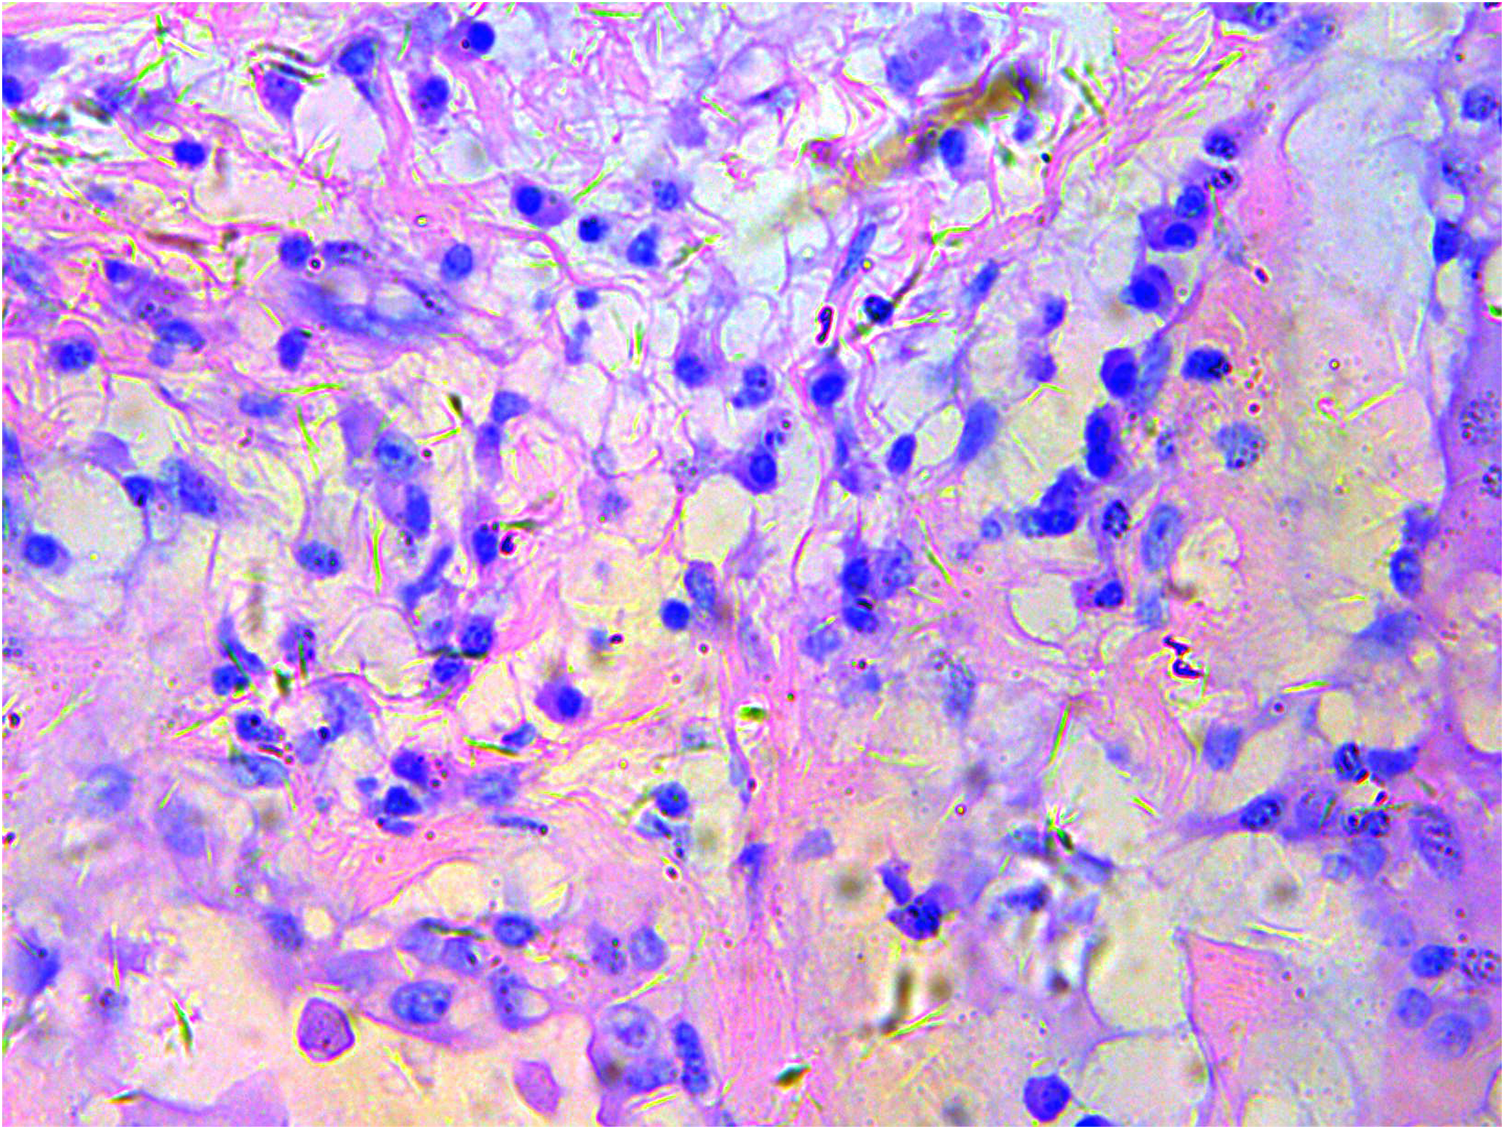

A gross pathological examination indicated a grayish-white, jelly-like mass with a size of 5 cm × 5 cm × 4 cm, and the tip was approximately 5 mm. No envelope was seen. Microscopic examination identified numerous fissures in the tumor tissue. Glandular ducts and microcystic structures were seen (Figure 2). The tumor stroma and mucosa were fibrous; the cells were epithelioid and either vacuolated or cuboidal. The cytoplasm was acidophilic and abundant; the nucleus was large and deeply stained. The karyoplasmic index was high, and the nucleolus was clearly visible (Figure 3). Immunohistochemistry showed calretinin (Figure 4), and CK5/6, CK, D2-40, WT-1, and vimentin were positively expressed. TTF-1, napsin A, CEA, CK7, CD31, CD34, and other markers were negative. The percentage of the Ki-67 positive index was approximately 40.

Figure 3

Epithelioid cells are vacuolar or cubic, with acidophilic and abundant cytoplasm and large deeply stained nuclei; H&E ×200.

The most common morphologic variants of epithelioid mesothelioma are tubular, papillary, solid, and trabecular. Psammoma bodies may appear in any of these variants. Other uncommon variants include micropapillary, adenomatoid (microcystic), clear cell, migratory, metaplastic, small cell, and lymphohistiocytic (8, 9). Generally, epithelioid tumors contain polygonal, vacuolated, ovoid, or cuboidal cells that mimic reactive mesothelial cells and respond to various types of injury. However, a poorly differentiated epithelioid tumor with pathological mitotic signs was seen in our patient (10).